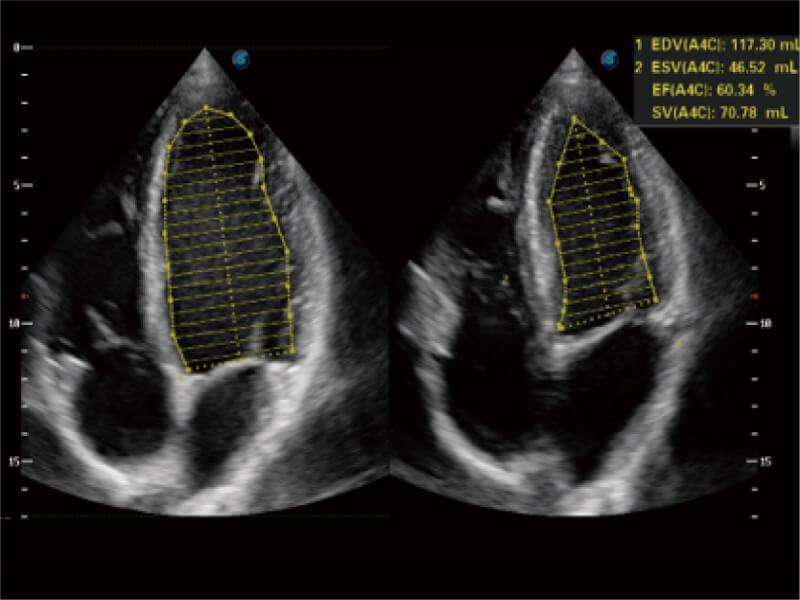

能夠基于左心室壁追蹤和辛普森法,自動(dòng)計(jì)算射血分?jǐn)?shù),支持多個(gè)可移動(dòng)點(diǎn)描跡,與手動(dòng)測(cè)量相比,極大節(jié)省了動(dòng)物醫(yī)生的時(shí)間和精力。